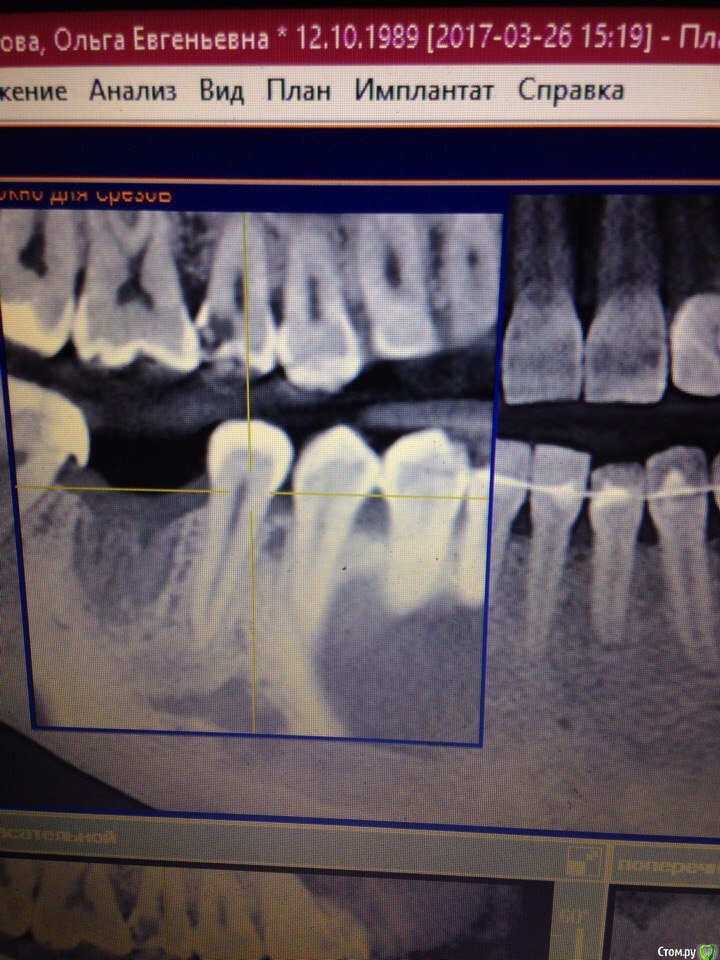

Fenixa89 Опубликовано 19 апреля, 2017 Поделиться Опубликовано 19 апреля, 2017 (изменено) Здравствуйте! На переднем нижнем зубе образовалась рецессия после удаления шестого зуба на той же нижней челюсти. Хирург ,который когда-то спасал меня от рецесии в том же месте, с помощью лоскутной операции ( хватило на 7-8 лет) сказал сделать КТ. На КТ довольно-таки глобальная очаговая резорбция кости челюсти в районе этого зуба.Решили делать повторную лоскутную операцию лишь потому, что зуб не шатается. Возник ряд вопросов: 1. Может ли быть связаны резорбция и рецессия с неудачными брекетами ? Сужали нижнюю челюсть: в результате в середине 2 зуба остались один выше, один ниже. Как раз один из них и проблемный.2. Резорбция получается возникла ещё 8 лет назад, когда в этом месте опустилась десна в первый раз?3. Может ли быть связано резкое опущение десны этом месте ( напомню: передние нижние зубы) и удаление шестёрки нижней. После удаления через 7 дней опустилась десна.4. Или же стоит исправлять прикус?Буду очень благодарна за ответы! Изменено 19 апреля, 2017 пользователем Fenixa89 Ссылка на комментарий

Fenixa89 Опубликовано 19 апреля, 2017 Автор Поделиться Опубликовано 19 апреля, 2017 http://forum.stom.ru/topic/20613-sovety-patcientam-obiazatelno-k-prochteniiu/ Фото и кт добавила Ссылка на комментарий